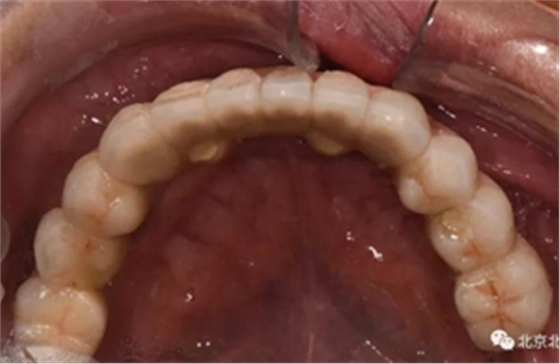

圖十四:口內(nèi)照

圖二十五:口內(nèi)照。